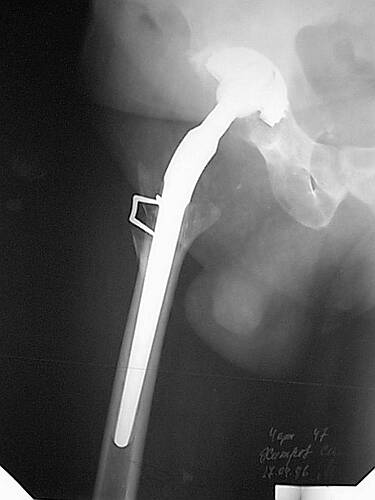

Наше общее мнение - проведение клиновидной остеотомии в зоне дополнительной точки опоры с ее иссечение и укорочением бедра, протезирование ножкой Вагнера.

Похожий случай представляем на ретгенограммах. Операция выполнена в 1996 г.